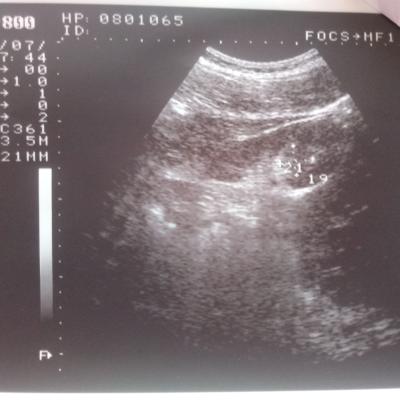

Добрый день! Моему сыну 15 лет. В его моче обнаружено большое количество эритроцитов. Узи почек показало "МКД обеих почек и киста правой почки". Назначение терапевта: уродан 1 ч/л×100 мл.×2 р.д. 30 дней,конефрон 1 таб×3 р.д. 30 дней. Скажите, пожалуйста, насколько это серъезно? Дело в том, что мой сын поступает в военную школу. Сами понимаете, там физические нагрузки. Можно ли нам там учиться с таким диагнозом? И какое лечение посоветуете? Нужно ли нам дополнительно сделать КТ или МРТ?

Ответ врача